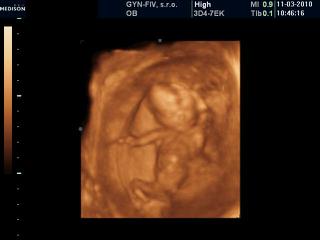

mac ano toto je povinnne a neplati sa za to.to len ked chces ist na to 3D alebo 4D 😉

ja som bola na 3D pred dvoma tyzdnami a urcite to stalo za to. Bola som v BA na Zahradnickej a stalo ma to 17E, na Kramaroch je to vraj raz tolko. Fotky mam v albume a hrozne sa z nich tesim (a hlavne manzel, pretoze nemohol ist so mnou priamo tam). Aj zopar videi mame, kde je vidno ako sa mrvi a hybe, pretaca sa... az mi slzicky vyhrkli ked som ho tam vtedy v ordinacii videla 😀 jednoznacne silny zazitok

Lulu - hej je to povinné, ale v Ružinove sa za to aj tak platí 42 E a keď chce niekto aj 3D- ten stojí ešte plu 72e. v stredu mi to presne sestrička čítala.

72E za 3D je naozaj nehorazne vela... Na Zahradnickej so vsetkym (CD s fotkami a videami bolo v cene) za 17... ved to sa neda porovnat. Za 72E by som na to asi ani nesla 😖

Dakujeme 😉 babo sa predvadzalo, mavalo, kopalo, tocilo sa zo strany na stranu... na jednej fotke vidno vsetky prsteky na rucicke, na inej aj rebra mozes spocitat... podla mna uzasna vec to 3D.

V kutiku duse som dufala, ze snad bude vidno aj pohlavie, ale este si musim par tyzdnov pockat 😉

zajtra sa asi pôjdem objednať na 4D ultrazvuk, aby aj manžel videl ten náš zázrak. u nás to stojí 35 EUR a je k tomu DVDčko, možno aj fotka, ale to neviem.

Mariann, áno, ja som z KK a idem sa objednať niekedy na koniec mája k Vojtaššákovi v PP. Boli sme u neho v prvom tehu a boli sme spokojní, aj keď 50 eur je dosť, stojí to za to.

toto "male" 3D robia medzi 14-16tt a potom "velke" 3D okolo 24tt

Andelik, ta fotka je úžasna..je to uplne niečo ine ako klasicky ultrazvuk 😵 😵 😵